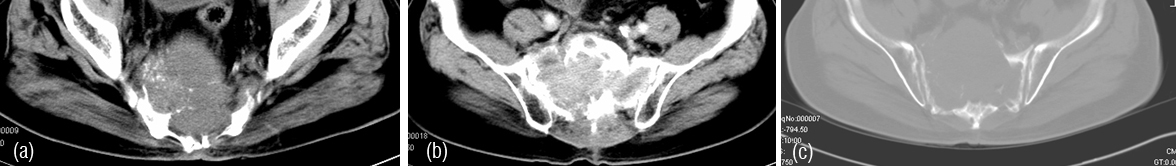

Radiologically, Sclerotic changes in the bone may be unifocal or multifocal. At times, lytic lesions may be also noted (Figure 8ab).

Figure 8: (a) Sclerotic myeloma – diffuse sclerosis of all the lumbar vertebrae. (b) Sclerotic lesion in the femur in Poems syndrome.